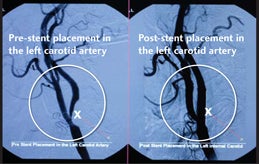

The interventionist may also place a stent, a tiny device made of metal mesh, at the site of the blockage to help prevent future blockages that could cause strokes.